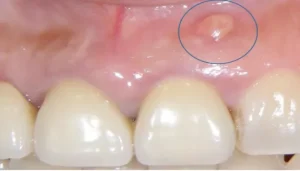

An abscess on the gum is a painful condition that occurs when a pocket of pus forms in the tissue surrounding a tooth. This infection